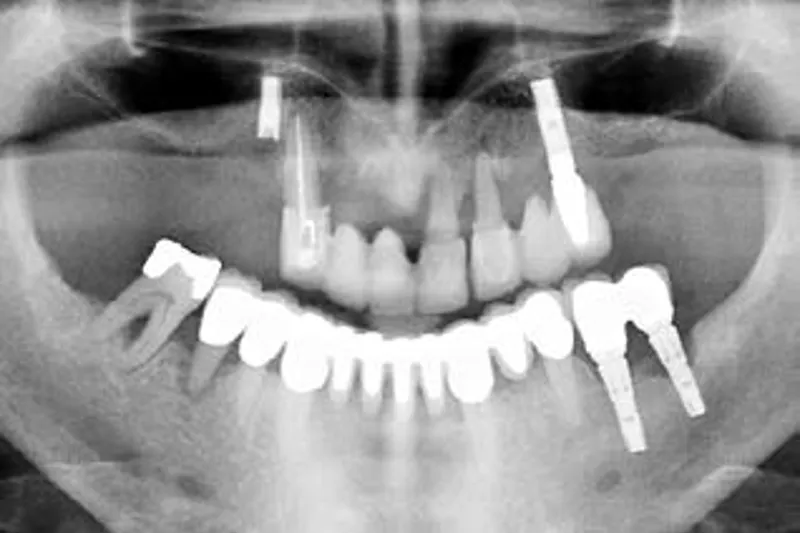

Periimplantitis er en plakassocieret sygdom i vævene omkring tandimplantater og er karakteriseret ved progressivt tab af knoglevæv omkring implantatet. Læsionerne ved periimplantitis er ofte større og progredierer hurtigere end læsioner ved parodontitis. Det progressive knogletab omkring implantater påvirkes af en række faktorer som fx plak, samtidig parodontal sygdom og almen sundhedstilstand. Der er ingen dokumenteret standardbehandling for periimplantitis, men man kan med fordel følge en behandlingsplan med samme elementer som ved behandling af parodontitis: Undersøgelse med henblik på at udrede de underliggende årsager til sygdommen, nonkirurgisk behandling, kirurgisk behandling og støttebehandling. Der er forskellige redskaber til brug ved nonkirurgisk behandling, men det er nødvendigt i hvert enkelt tilfælde at vurdere, hvor tilgængelige implantatoverfladerne er. Kirurgisk behandling sigter primært efter at skabe bedre adgang til de kontaminerede implantatoverflader og dermed muliggøre effektiv fjernelse af biofilm. Der må tages stilling til, hvorvidt det kirurgiske indgreb skal være resektivt, genopbyggende eller en kombination af disse to. Man må ligeledes overveje, hvordan overfladerne skal dekontamineres. Efter den kirurgiske behandling skal patienterne indgå i et vedligeholdelsesprogram med henblik på at holde implantaterne sygdomsfri.

Peri-implantitis is a plaque-associated disease in tissues around dental implants, characterised by progressive loss of implant-supporting bone. The size of peri-implantitis lesions tend to be larger in size and progress more aggressively than periodontitis lesions. Progressive loss of implant-supporting bone is influenced by a number of factors e.g. plaque, concomitant periodontal disease, and systemic health status. There is no gold standard in treatment of peri-implantitis, but it is advantageous to follow a structured path similar to the treatment steps in periodontal therapy; examination aiming to find the underlying causes of disease, non-surgical treatment, surgical treatment, and supportive treatment. Several different tools are available for non-surgical treatment, but the accessibility of the implant surface must be considered in every case. Surgery aims primarily to provide better access to the contaminated implant surface in order to achieve effective biofilm removal. A decision must be made over, whether the surgical approach should be resective, reconstructive, or combination thereof. Also, the means of surface decontamination must be considered. Following surgery patients need to be enrolled in a maintenance-program in order to keep the implants free of disease.